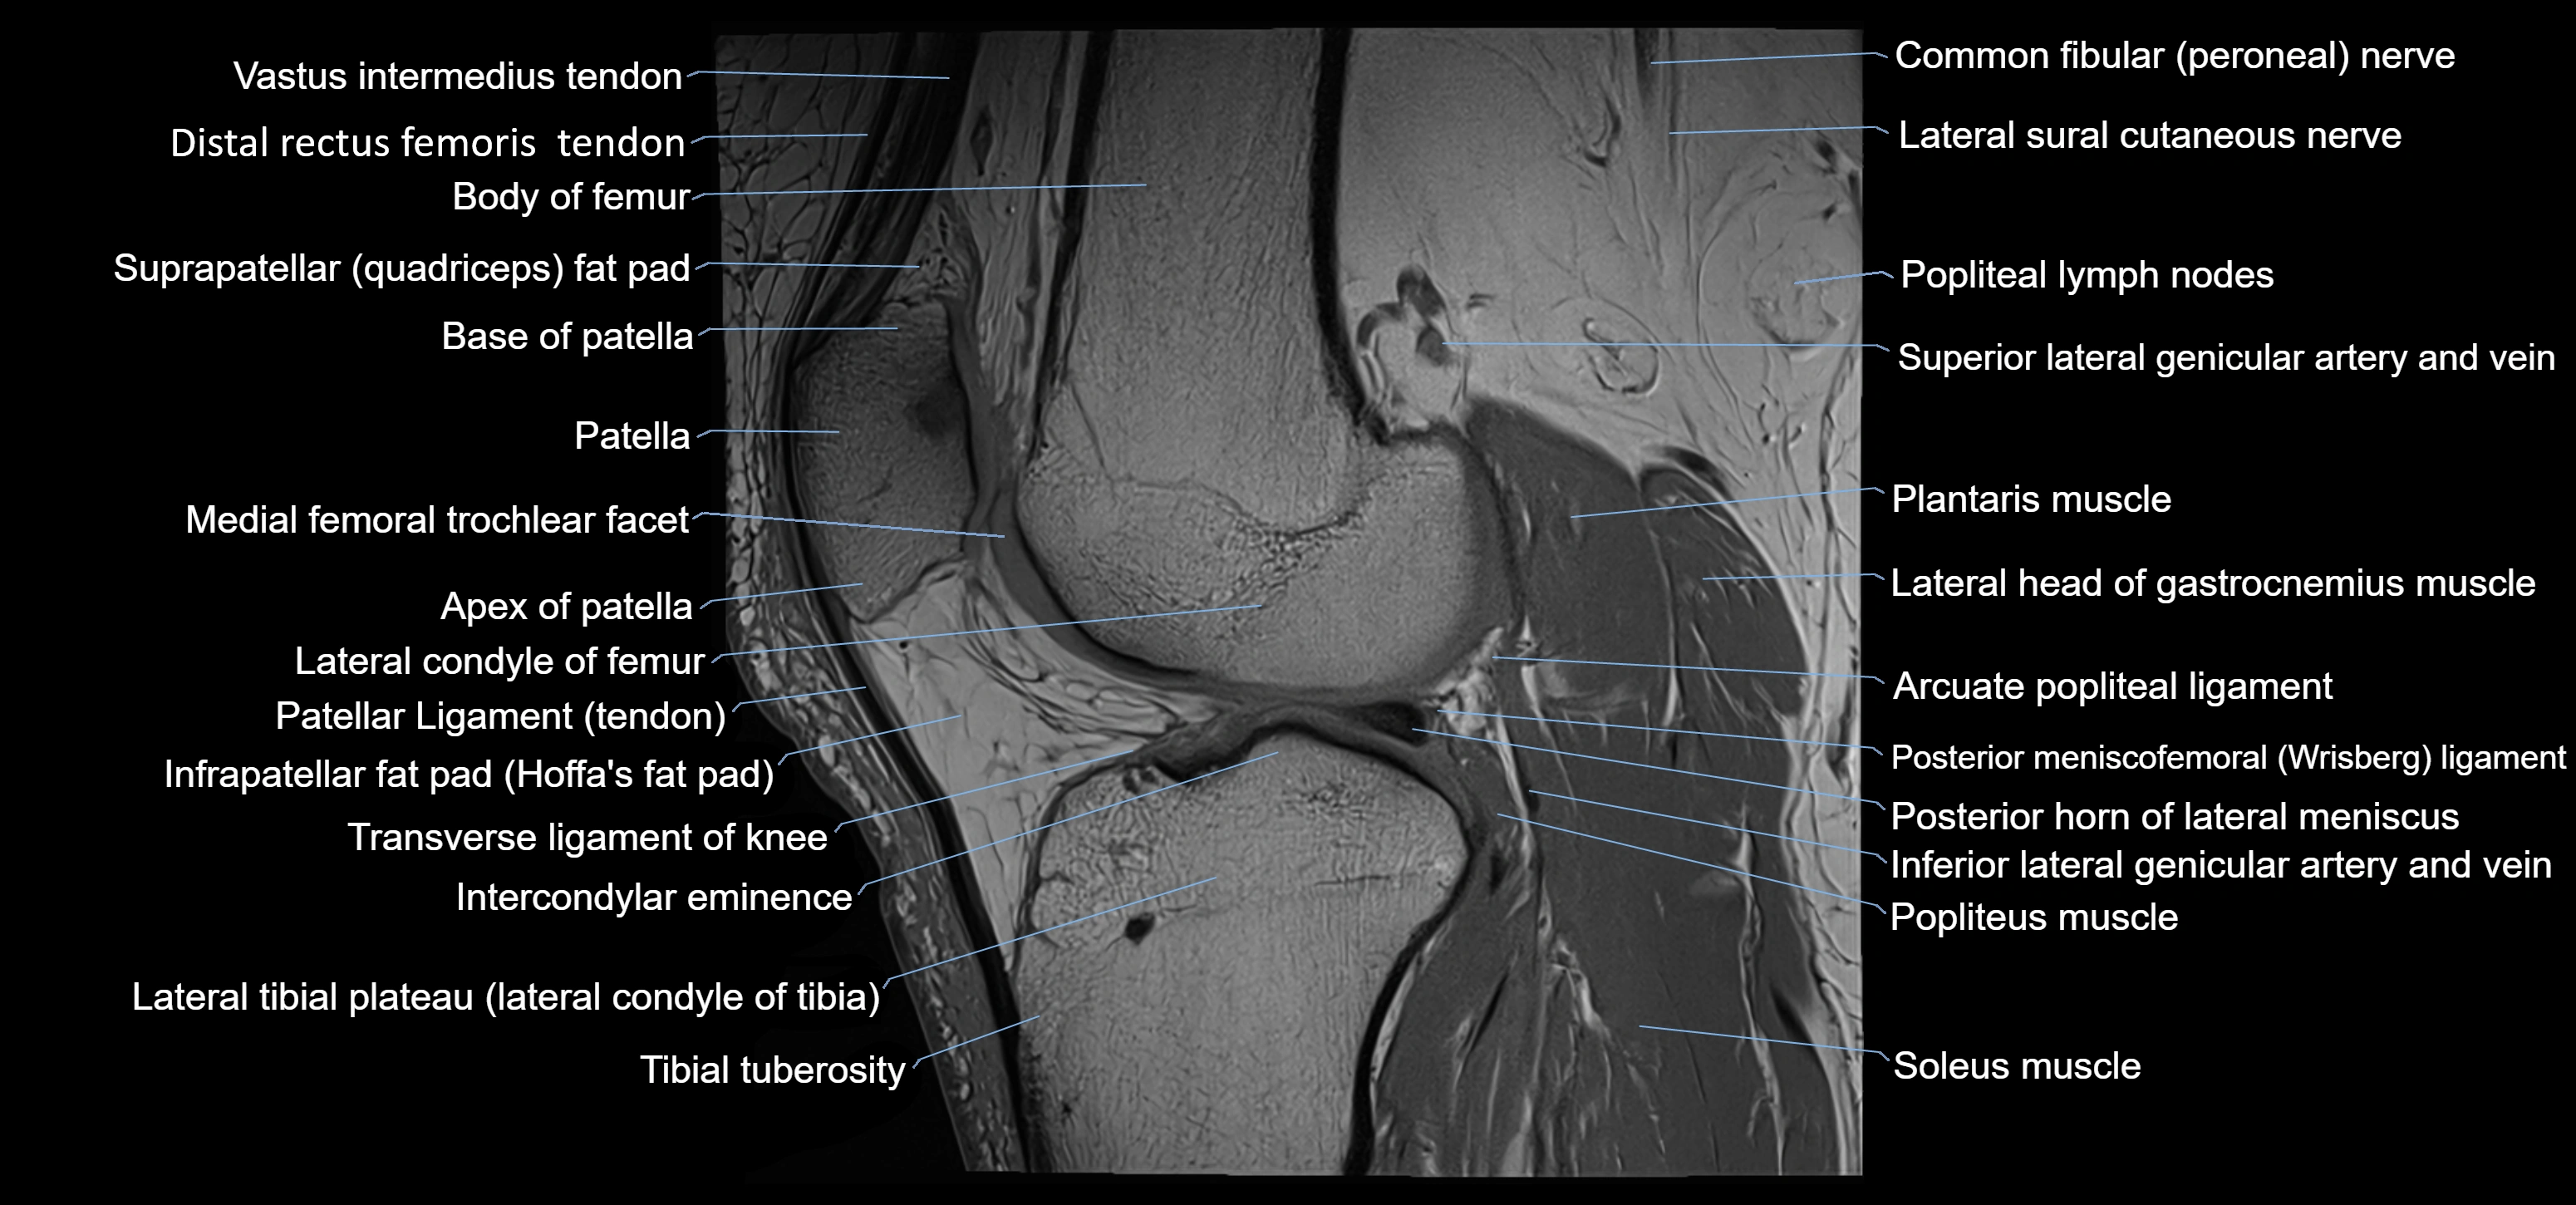

- Apex of patella

- Base of patella

- Body of femur

- Distal rectus femoris tendon

- Distal vastus intermedius tendon

- Femoral condyle articular cartilage

- Inferior lateral genicular artery

- Inferior lateral genicular vein

- Infrapatellar fat pad

- Intercondylar eminence

- Lateral condyle of femur

- Lateral head of gastrocnemius muscle

- Oblique popliteal ligament

- Patellar tendon (patellar ligament)

- Plantaris muscle

- Popliteus muscle

- Posterior cruciate ligament

- Posterior horn of lateral meniscus

- Posterior meniscofemoral ligament

- Soleus muscle

- Superior lateral genicular artery

- Superior lateral genicular vein

- Suprapatellar fat pad

- Tibial tuberosity

- Transverse ligament of knee

- Trochlear groove